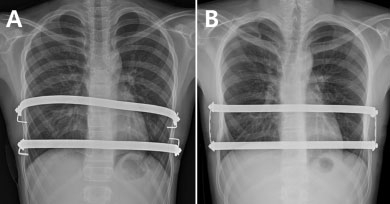

가톨릭대 인천성모병원 정진용 교수팀은 기존 2개의 교정 막대를 개별적으로 고정하는 ‘분리고정 수술법’(사진A)과, 각 교정 막대 양 끝을 작은 금속 막대로 연결해 사각형 형태로 고정하는 ‘사각고정 수술법’(사진B)의 결과를 비교 분석했다.

정 교수팀은 2011년 9월부터 2016년 1월까지 2개의 금속막대를 삽입한 너스수술 환자 86명을 교정 막대의 양쪽 측면을 각각 고정한 A군(44명, 사진A)과 각 교정 막대를 세로형 막대와 연결해 사각형 형태로 고정 시킨 B군(42명, 사진B)으로 나눴다.

연구결과, 수술 후 A군에서 막대 전위로 재수술한 경우가 6.8%(3명)인 데 반해 B군에서는 재수술이 단 한 건도 없었다. A군과 B군에서 수술 전후 핼러 지수 차이는 나타나지 않았다.

이를 통해 연구팀은 사각고정 방법이 분리고정 수술에 비해 막대 전위를 보다 효과적으로 방지하고, 이로 인한 재수술을 최소화할 수 있다는 결과를 확인했다.